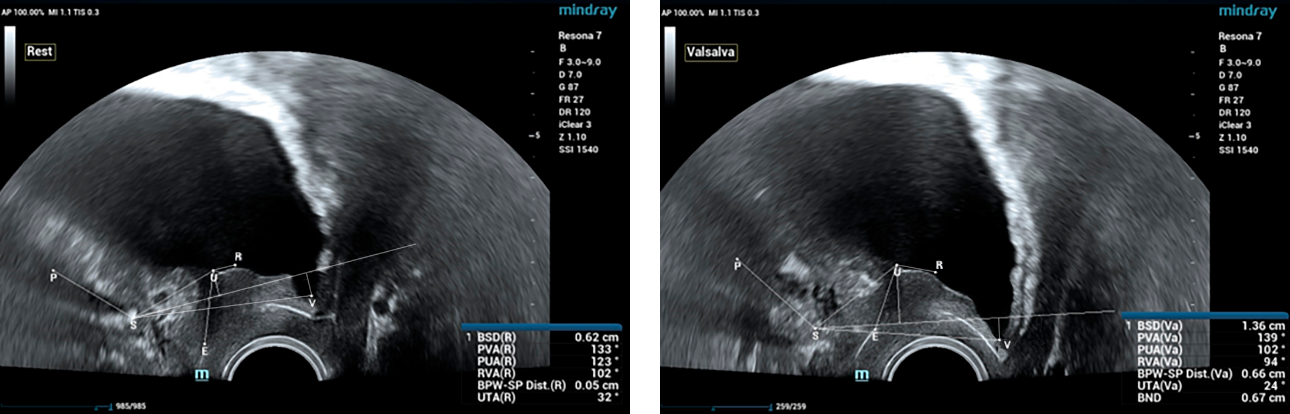

One of the important causes of stress urinary incontinence is hypermobility of the urethra, for the diagnosis of which, during ultrasound of the pelvic floor, functional tests (Valsalva and / or cough) are required. In this clinical case, the PVA, RVA and PUA indicators will be rejected by more than 20┬░. In this clinical case, PVA ŌĆō 134┬░, RVA ŌĆō 82┬░ and PUA ŌĆō 119┬░.

The anatomical length of the urethra is determined at rest and with a Valsalva test. Normally, this indicator can vary from 30 mm to 42 mm. In addition, with hypermobility of the urethra, the expansion of the proximal and middle urethra at rest and during straining can be determined. In this patient R. at rest, the width of the urethra in the proximal part is 7 mm, when strained ŌĆō 8 mm.